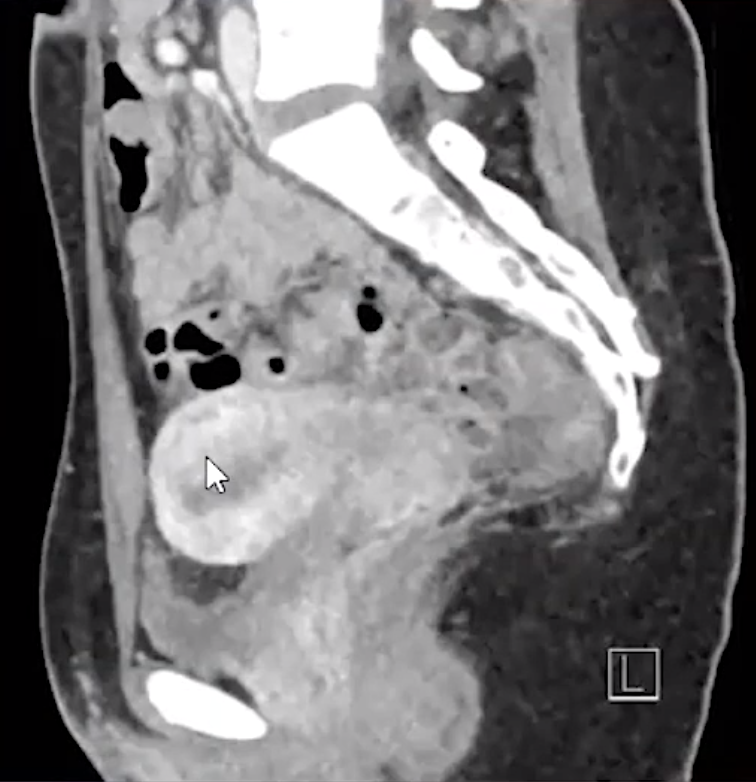

• Dermoid cyst = most common mass to cause

• Look for areas of increased echogenicity = fat

• Look for dot-dash sign = alternating echogenic dots and dashes = represents calcifications and hair

Dot-Dash sign seen with dermoid cysts